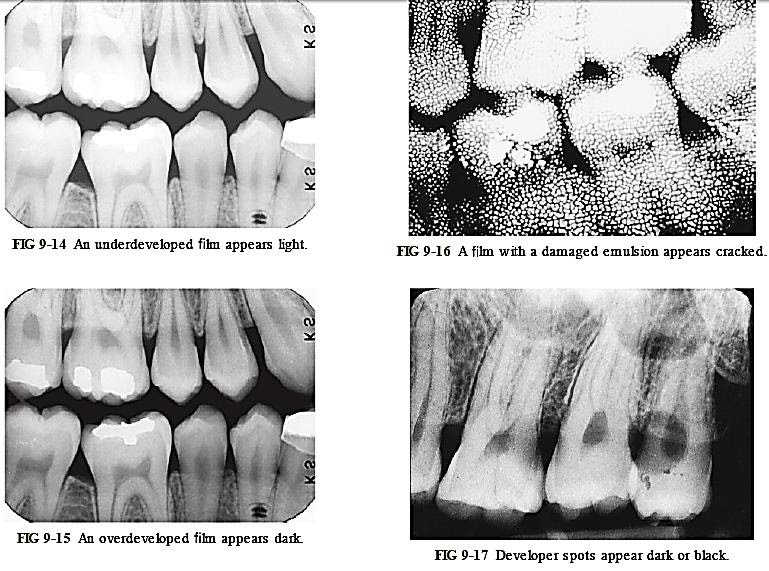

Processing Errors Dental X Rays . — these technique errors have already been covered in detail in relation to the three main projections used in dentistry, namely:. — here we are going to share the various types of faults in radiographs caused due. The most common being improper exposure settings. As well as generalised fogging caused by exposure of the whole film to light, there are. — errors and artefacts in dentomaxillofacial include positioning errors in intraoral techniques, panoramic. Table 5 lists various errors that can occur with. it is important for the clinician to be able to understand errors when they occur and how to correct them. Incorrect exposure can be caused by many factors; dental radiography qa processing errors light contamination. Recognize items needing to be removed. exposure errors time setting.